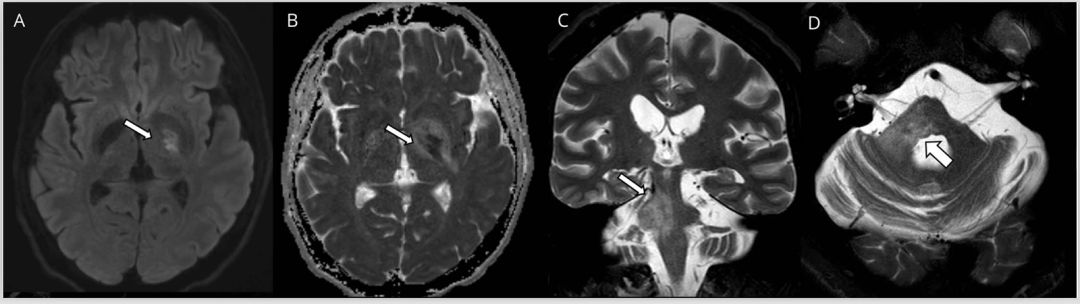

多发性硬化(MS)是中枢神经系统的获得性炎性脱髓鞘疾病,在MRI上病灶通常为卵圆形且界限清晰,T2和FLAIR序列呈高信号改变(图1)。在慢性病变过程中当轴突受损时,T1序列上可见低信号的黑洞征,但急性期也可能见到。新发病灶在3天到3个月内(平均3周)可见强化。虽然MS病灶会出现弥散受限,但当弥散发生变化时,弥散率通常会增加。当存在弥散受限时,特别是多发病灶和不在典型部位时,应考虑其他病因,例如SS或血管炎。

MS的病灶通常发生在脑室周围、胼胝体周围、深部白质、皮层和近皮层部位、脑干、小脑以及视神经和脊髓。在T2 *序列上的中心静脉征有助于MS病变与其他炎性和非炎性疾病(包括NMOSD)的鉴别,超过80%的MS病变位于静脉周围。而相比之下,NMOSD为32%,CNS血管病变为14%。

图1多发性硬化症患者的MRI影像。轴位T2加权(A,B)显示脑桥外围界限清楚的卵圆形病灶(箭头)。矢状位FLAIR图像(C,D)显示胼胝体下表面的病灶(C)和垂直于胼胝体的病灶(Dawson指征)(D)。